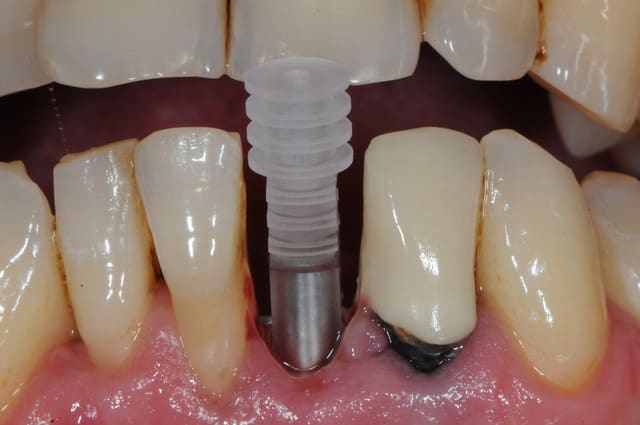

je me permet de ressusciter ce poste car j'ai placé la prothèse il y a un mois.

photo 1: début du cas

photo 2: fin d'intervention

photo 3: j+3mois

photo 4 +5: prise d'empreintes

photo 6-7-8-9: couronne finie.

merci de votre attention :)

PS: le patient ne veux pas faire celle d'à coté.

grr, moi ça me démange...